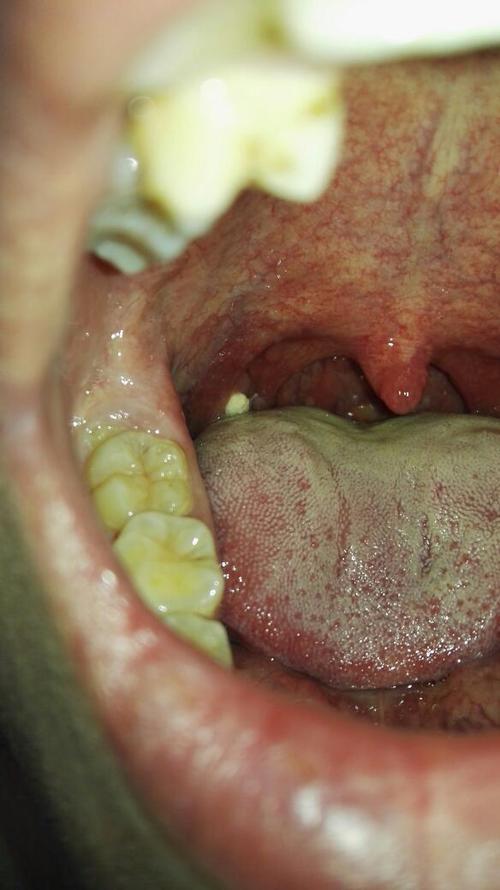

鹅口疮 (雪口病)

- 外观:像一层白色奶垢或豆腐渣样的膜,可以轻易擦掉,但擦掉后下方会露出一个红色的、轻微出血的创面,如果擦不掉,就不是鹅口疮。

- 位置:常见于舌头、内颊、上颚和嘴唇内侧。

- 感觉:可能有轻微的疼痛或烧灼感,婴儿可能会因此拒绝吃奶。

- 原因:由白色念珠菌(一种真菌)感染引起,常见于婴幼儿、老年人、身体免疫力低下者或长期使用抗生素的人。